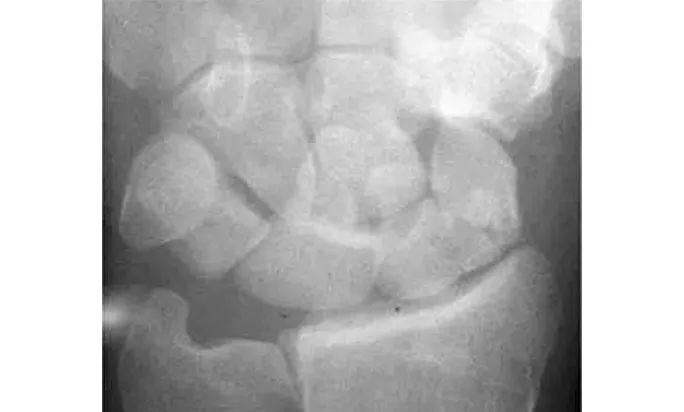

Analyze - 腕骨弧线正位弧线不连续,侧位明显脱位。

月骨脱位月骨周围脱位,苹果歪了,香蕉还在

Case 分析

1.月骨-三角骨间隙不平行,存在重叠。

2.钩状骨和月骨也存在重叠。

3.桡骨、月骨、舟骨近极和头状骨近极平行关系存在。

4.三角骨、钩骨、头状骨远极、大多角骨和舟骨远极平行关系也存在。

5.头状骨和舟骨骨折。

诊断:经舟骨、经头状骨月骨周围骨折-脱位。